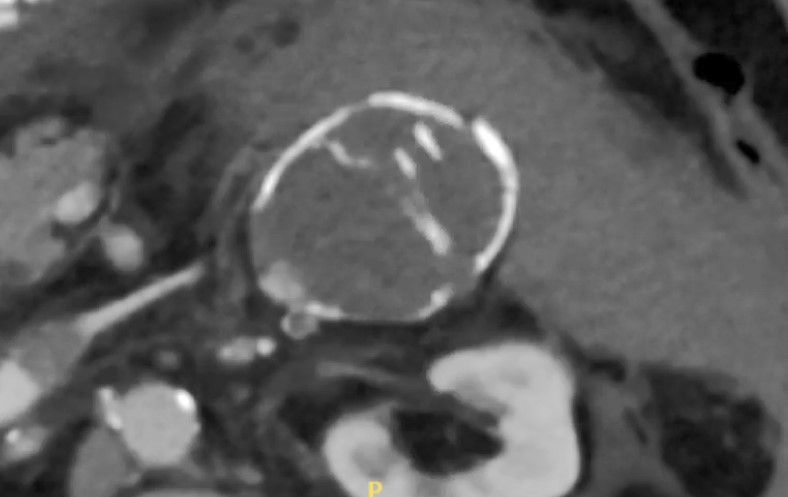

A 65-year-old male with a medical history of hypertension and chronic obstructive pulmonary disease (COPD) presented to our hospital’s emergency department (ED) with a complaint of severe left-sided abdominal pain of 2 hours’ duration. He stated that the pain was mainly in the left flank with radiation into his back; he denied pain with urination and hematuria. The patient stated that he had never experienced pain of this nature. He denied fever, chills, chest pain, and shortness of breath. He did admit to active tobacco use with a 50 pack-year smoking history and had undergone a previous umbilical hernia repair with mesh. On physical exam, the patient was hypotensive with a systolic blood pressure of 80 mm Hg; he was anxious, diaphoretic, and obviously in distress. He displayed tenderness to palpation of the left side of his abdomen with guarding; on vascular exam, his femoral and distal pulses were palpable. In the ED, a computed tomography (CT) scan with IV contrast was obtained, revealing a 6-cm left renal artery aneurysm with active extravasation and a large retroperitoneal hematoma (Figure 1).